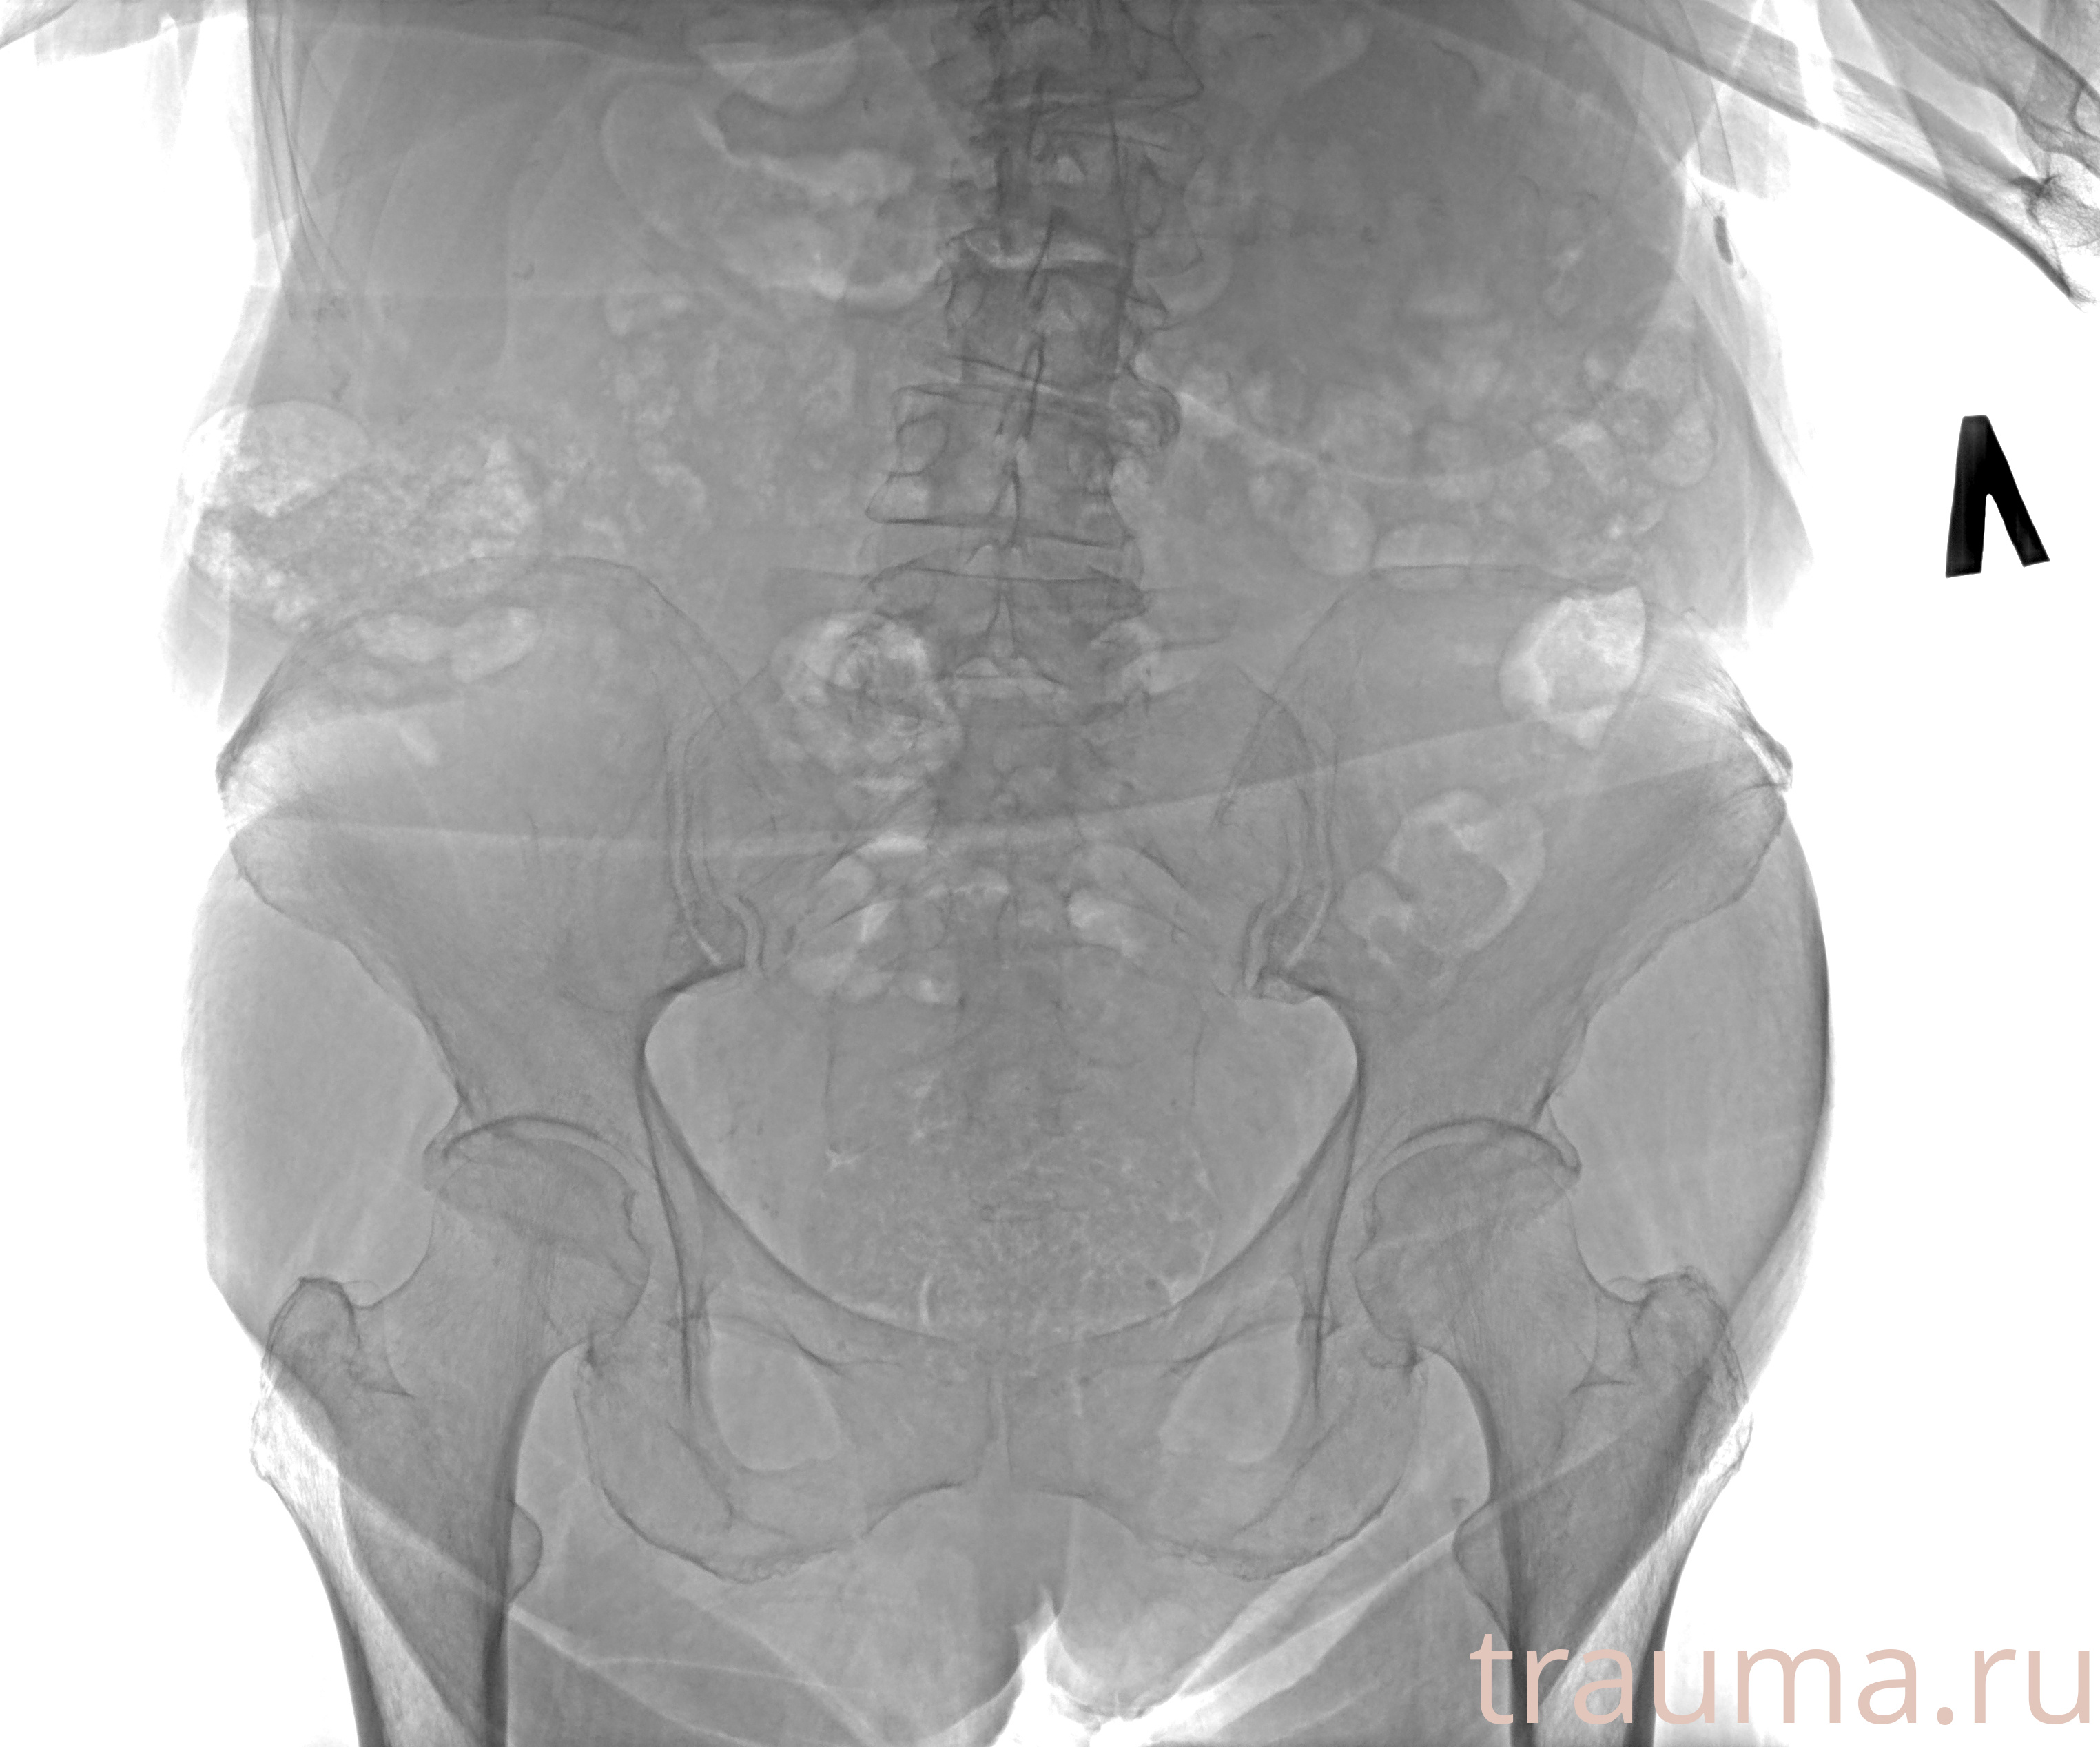

Рентгенограммы

Рентген на дому: по вашему адресу приезжает врач-рентгенолог, травматолог-ортопед с мобильным рентгеновским аппаратом, проводит диагностику травмы или заболевания, делает необходимые рентгенограммы, дает рекомендации по дальнейшему лечению. Получить качественные снимки в домашних условиях возможно благодаря уникальной методике, разработанной МосРентген Центром для института  Склифосовского

при переломе шейки бедра и пневмонии от компании МосРентген Центр - партнера Института имени Склифосовского